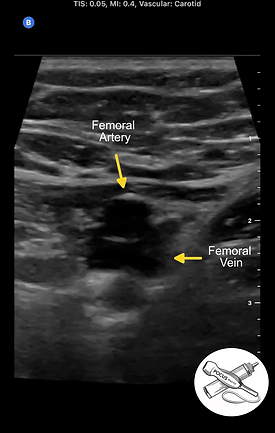

Zone 2: Femoral Vein and Artery from Greater Saphenous Vein to Adductor Canal

After the Greater Saphenous Vein exits the Common Femoral vein, it changes its name to the Femoral vein. The Femoral vein and artery travel down the medial thigh until they reach the adductor canal and dive posteriorly.